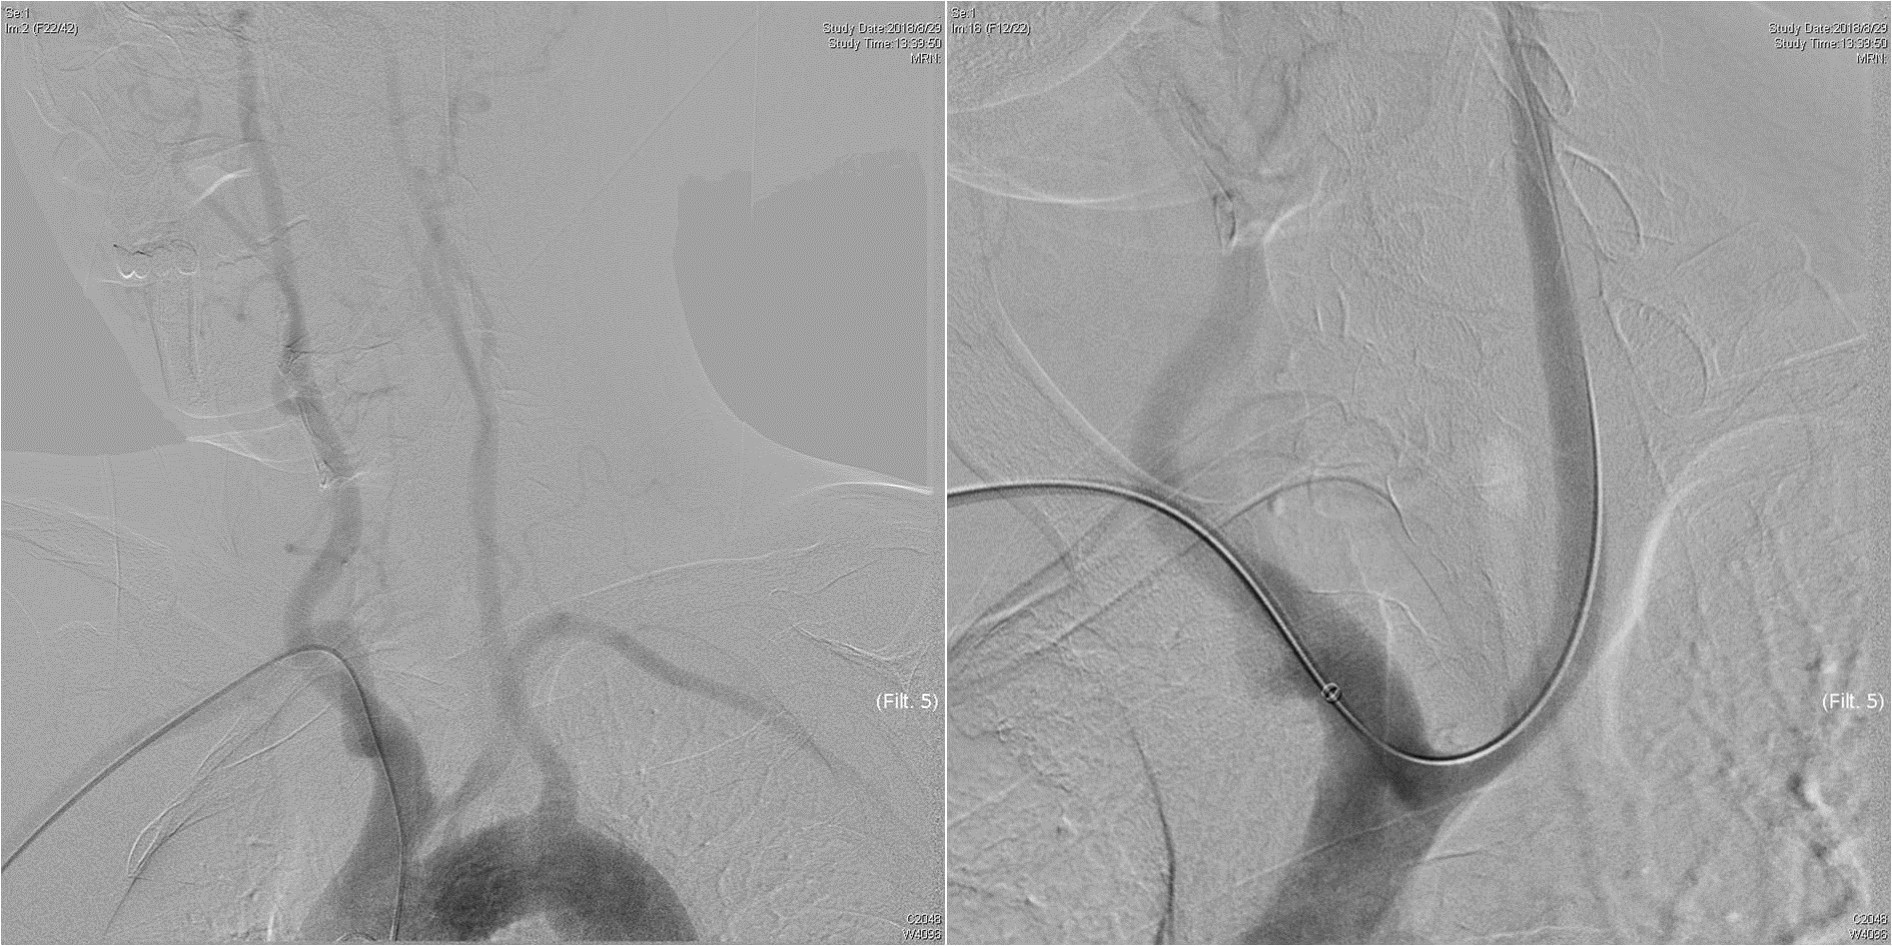

术前CTA提示王先生的主动脉弓形为“牛”型解剖变异(左侧颈总动脉从无名动脉发出,图1),颈总动脉起始部及颈内动脉均存在斑块狭窄,为手术增加了难度,经过仔细讨论分析病情,血管外科吴巍巍主任、赵克强教授决定“另辟蹊径”,从患者右上肢入路,实施微创颈动脉支架手术,同期解决颈总及颈内动脉两处病变。经过充分的术前准备,吴巍巍主任和赵克强教授在麻醉科医师的保驾下联手为王先生安全实施颈动脉微创支架植入术(图3、4),避免了王先生今后再次发生严重的脑卒中事件。术后返回病房,精准调控血压、心率,5天后王先生顺利康复出院。

图2-1 经右上肢造影并建立入路

图2-2  评估颅内情况